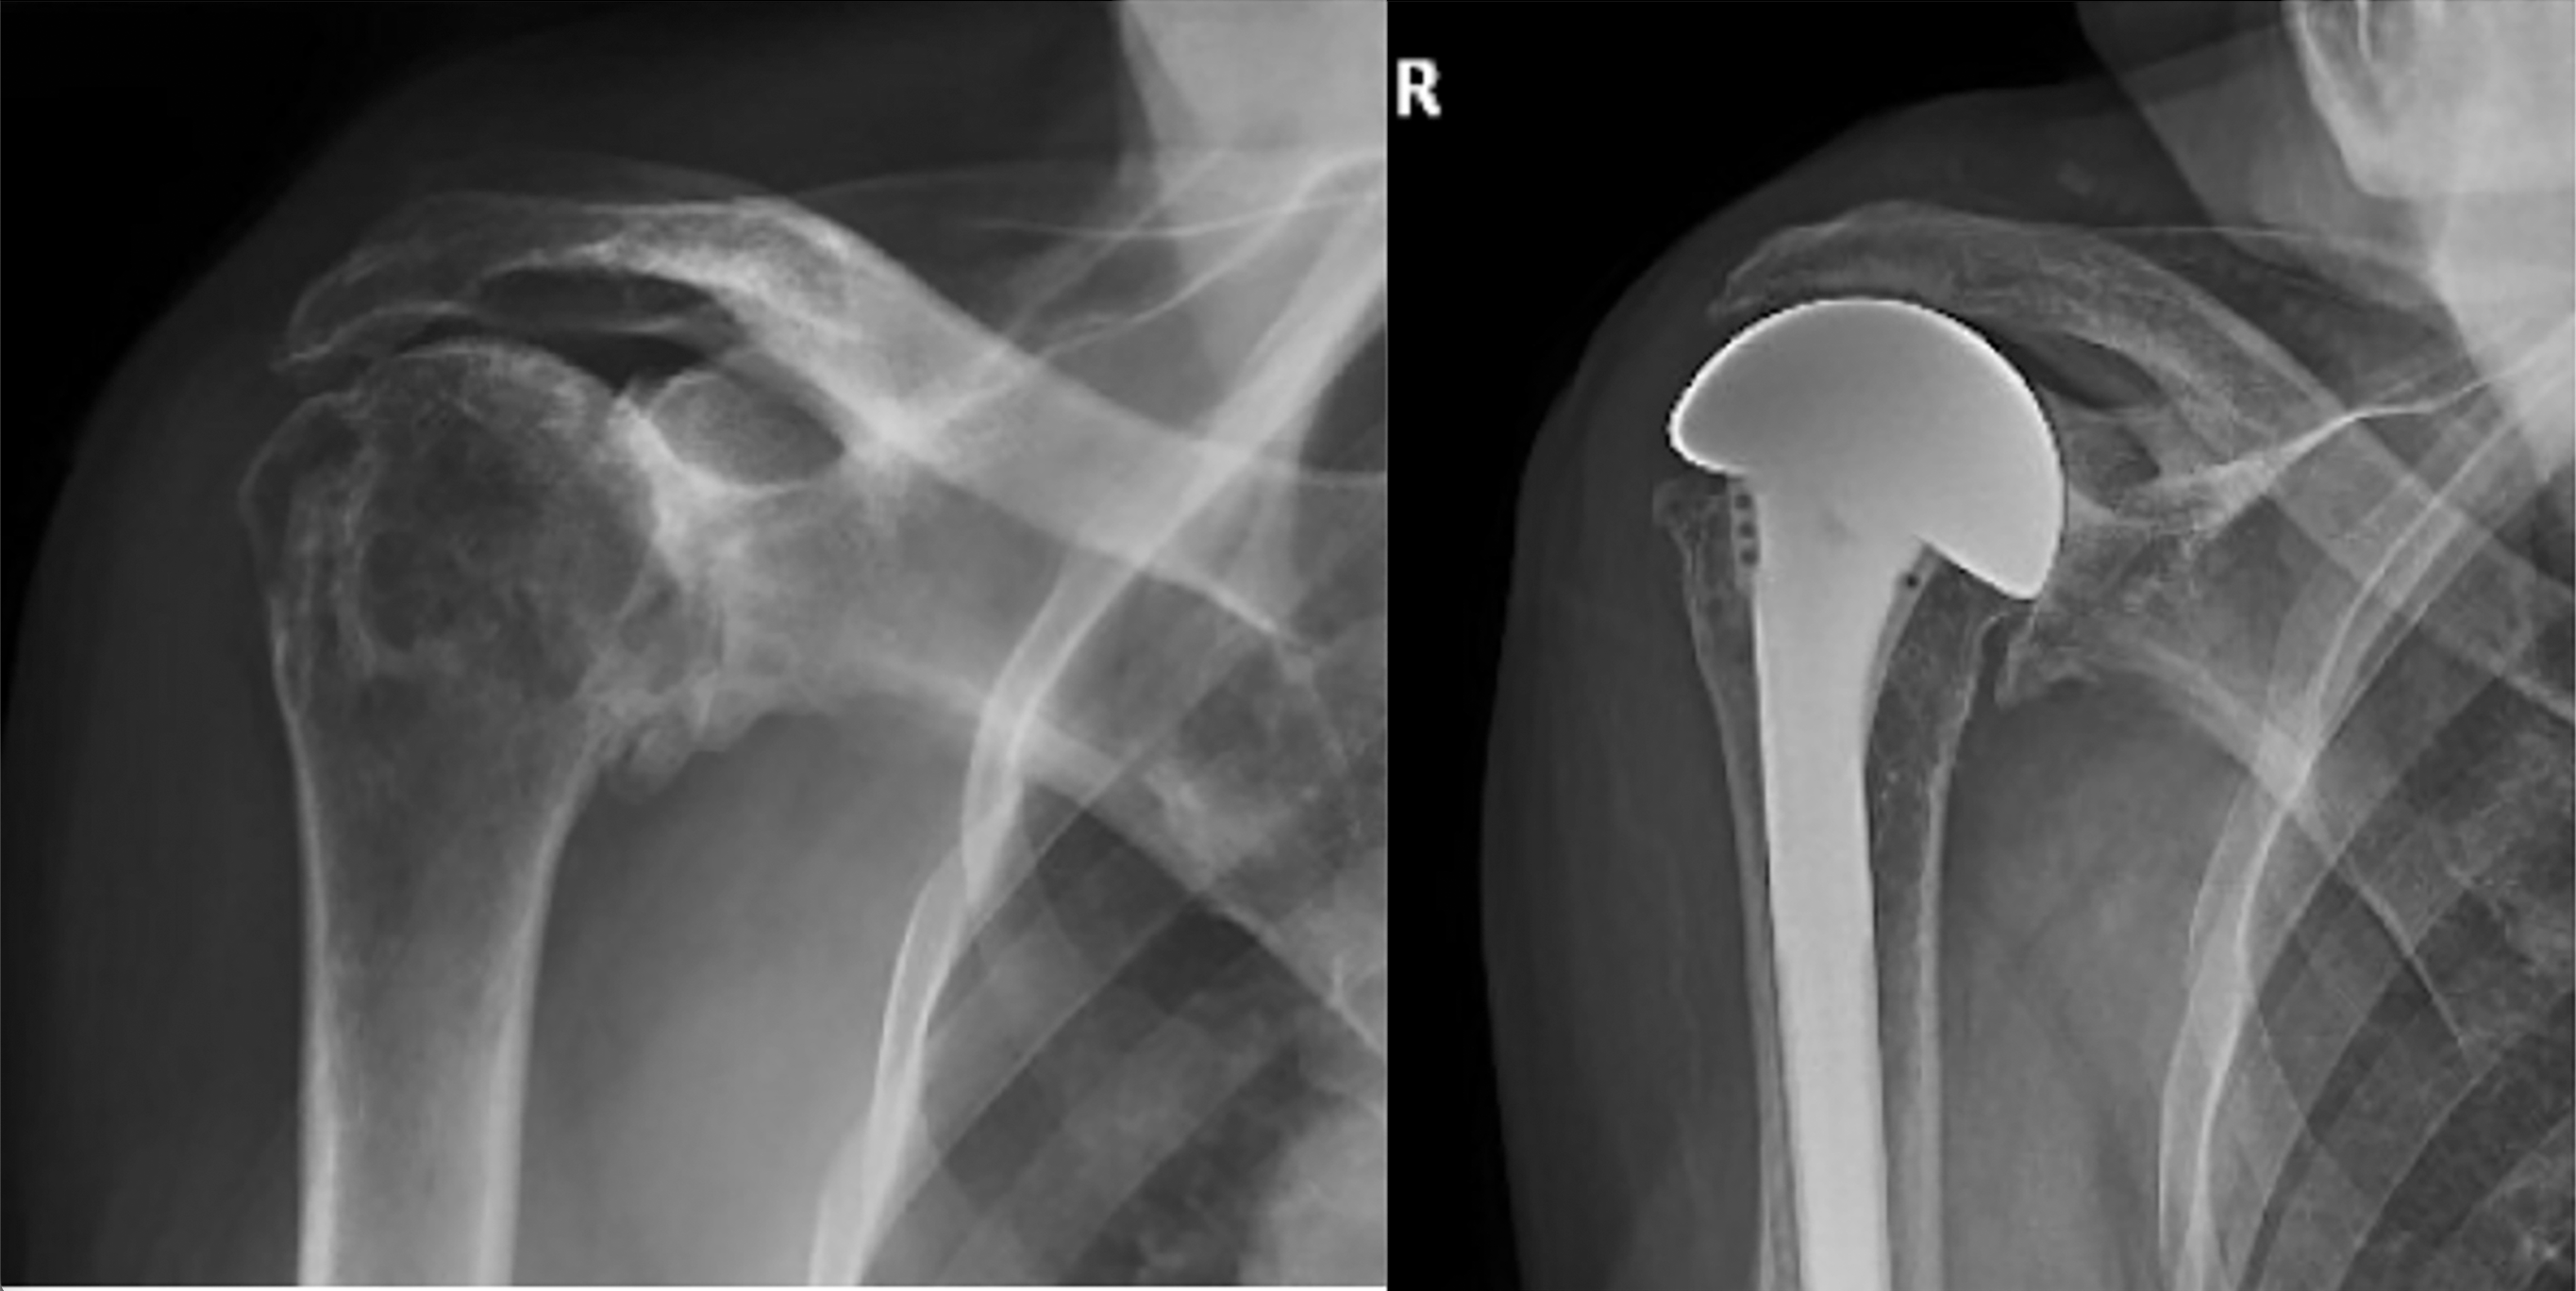

Case 1: A woman rancher in her early 60’s with arthritis, irreparable subscapularis, supraspinatus, and upper infraspinatus tears, and retained active elevation above the horizontal. Her preoperative and postoperative x-rays are shown here.

Case 2: An active woman in her 60’s with cuff tear arthropathy of the left shoulder after two failed rotator cuff repairs was referred for consideration of a reverse total shoulder arthroplasty. She has seronegative rheumatoid arthritis treated with prednisone, Avara, and methotrexate. Her preoperative x-ray shows diminished bone density, placing her at increased risk for acromial/spine fracture with a reverse total shoulder.

At 4.5 years after her CTA-H procedure she reported that she had returned to her desired activities. Her shoulder was comfortable and able to perform 10 of the 12 functions of the Simple Shoulder Test, including the ability sleep on that side, to internally rotate the arm to tuck in her shirt behind her, to wash the back of the opposite shoulder, to lift eight pounds to shoulder level, as well as to toss and throw a ball. Her SANE score was 100. She could actively elevate her arm to 140 degrees.